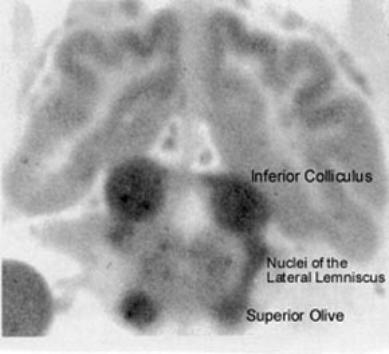

| Blood flow in the brain: Autoradiogram of the brain of a cat 60 seconds after injection of a radioactive tracer shows the greatest perfusion (thus greatest blood flow) in nuclei of the brainstem auditory pathway (from Kety 1962, with permission from Columbia University Press). |